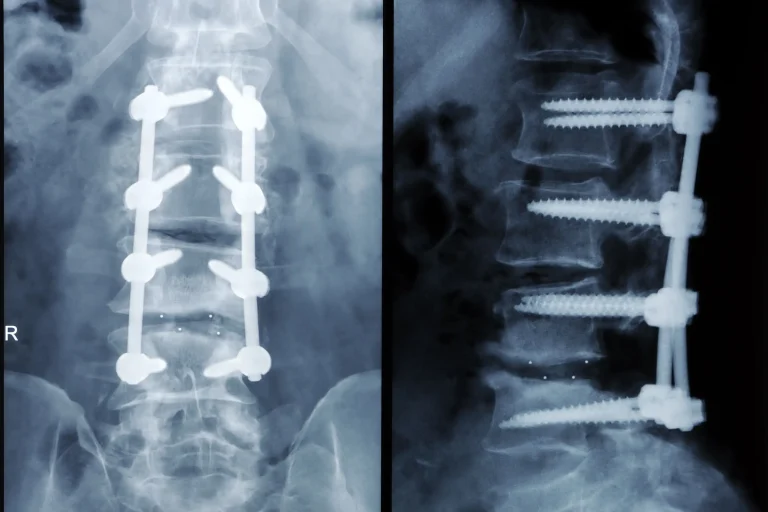

Spinal Fusion Surgery X-ray images showing spinal fusion with screws and rods.

Deuk Spinal Fusion

When performed by Deuk Spine Institute at the recommended treatment levels, a guarantee is available for purchase.